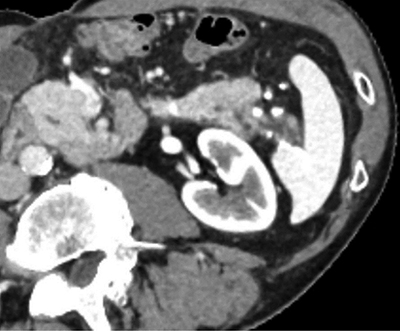

Figure 1

CT scan in arterial phase, showing caudal division of the tail of the pancreas and chronic pancreatitis changes posteriorly.